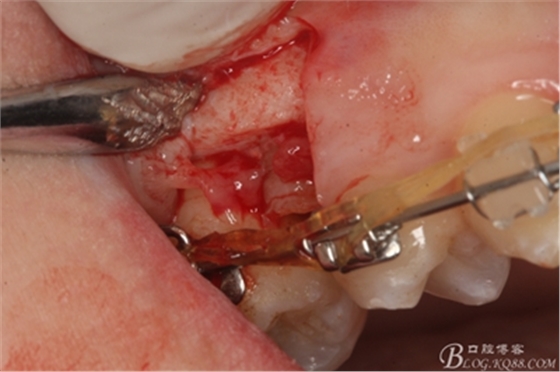

圖8.因16與14合面的間隙僅2mm左右,牙根無法合向脫位,如何考慮15牙根的脫位將是最大問題。高速手機(jī)去除牙間隙內(nèi)的覆蓋在15牙根表面的牙齦組織

圖10.去除牙齦組織后。露出15牙根斷面,合面無法脫位